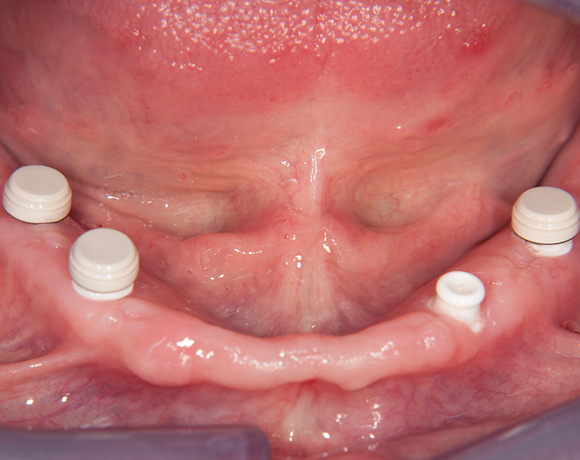

Fixierung einer Unterkiefervollprothese mit vier Implantaten

Mit Implantaten und dem Locatorsystem lassen sich Prothesen gut fixieren und geben einen guten Halt zum Essen und Sprechen

61 jähriger Patient, im Ober- und Unterkiefer mit Vollprothesen versorgt. Der Patient litt darunter, dass seine Unterkieferprothese keinen richtigen Halt hatte. So wurde ihm vorgeschlagen mit vier Implantaten und dem Locatorsystem die Prothese am Unterkiefer zu fixieren und damit einen hohen Komfort beim Essen und Sprechen zu ermöglichen. Der Patient entschied sich für eine metallfreie Versorgung. Es wurden Zeramex® P Implantate von Dentalpoint AG verwendet, für die Matrizen das System der Fa. Valoc das Novalocsystem gewählt. Die Verstärkung der Prothese wurde metallfrei mit einem PEEK – Gerüst gewährleistet.